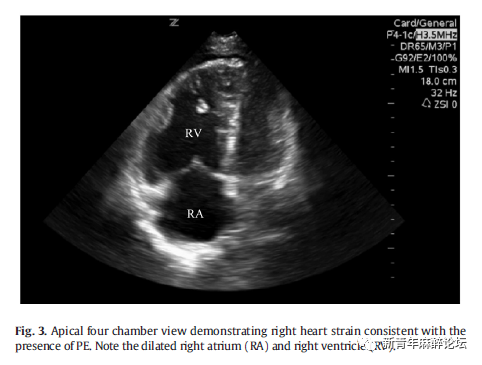

2.2.第二步:肺栓塞

因肺栓塞(Pulmonary embolism,PE)导致心脏骤停的患者占4.0–7.6%。这些患者至出院时的存活率(6.7%)高于其他 PEA 患者(1.3%)[5,17-20]。因此,急诊科医师在所有心跳骤停患者中快速且准确地评估PE至关重要。要评估并诊断PE,检查者需鉴别出右心张力增加的迹象,如增大的右心室和相对较小的左心室。(Fig.3)如存在右心张力增加,急诊科医师应考虑将PE作为引起PEA的原因。